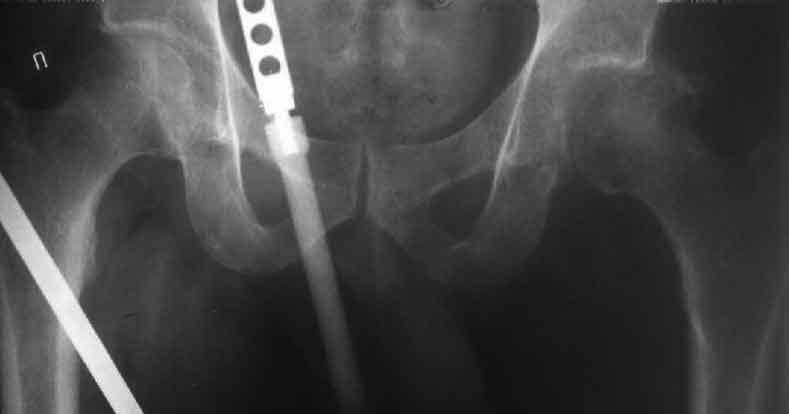

Насчет 8 см согласен с А.Н. Челноковым, это наверное ортопедическое за счет приводящей, сгибательной контрактуры и, возможно, колена. на ликвидацию укорочения у нас обычно уходит около 2-х нед. снимки в приложении, возможно не очень показательные, но других с ходу не нашел, завтра еще поищу.